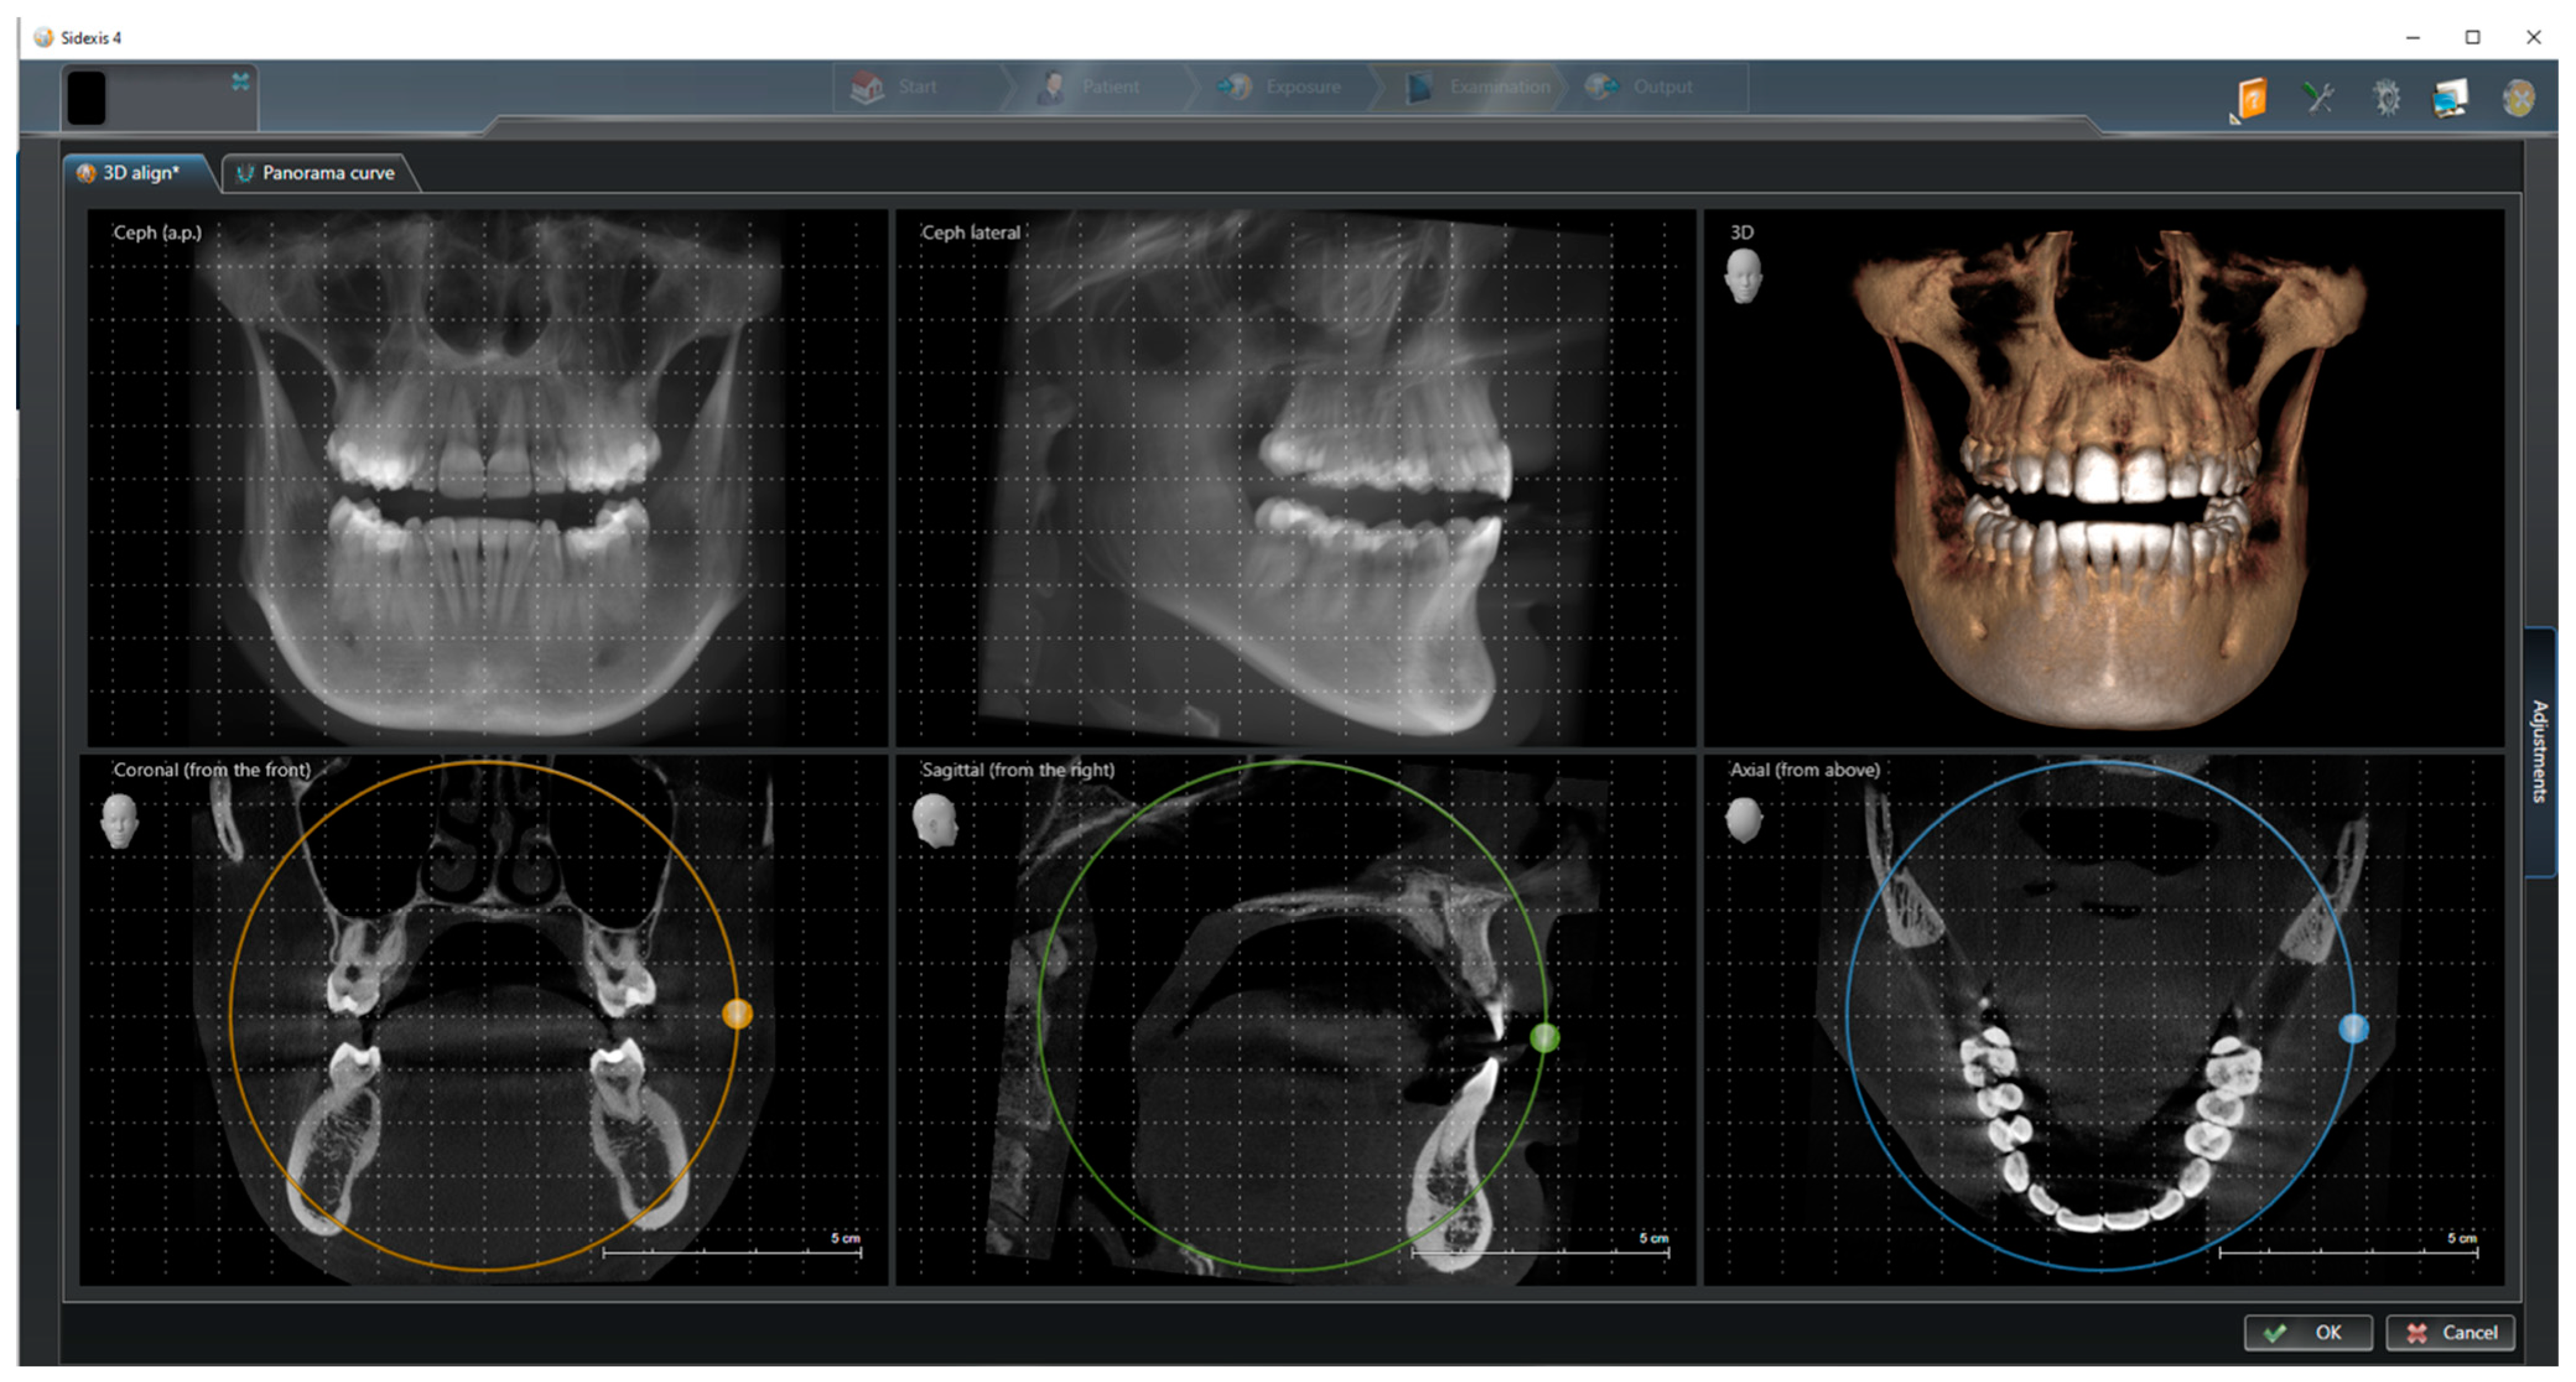

In the first step, the DICOM data of each patient were opened using SIDEXIS (version 4.3, Dentsply Sirona, Bensheim, Germany), and the patient position was corrected by adjusting the tilt and rotation. For this purpose, the coronal, sagittal, and axial sectional images were aligned parallel to the horizontal and transverse axes by shifting the drag points (Figure 1). The alignment of the patient’s position was necessary to ensure that all subsequent measurements took place in a correct horizontal plane.

Figure 1.

CBCT alignment to correct patient position by adjusting the tilt and rotation.